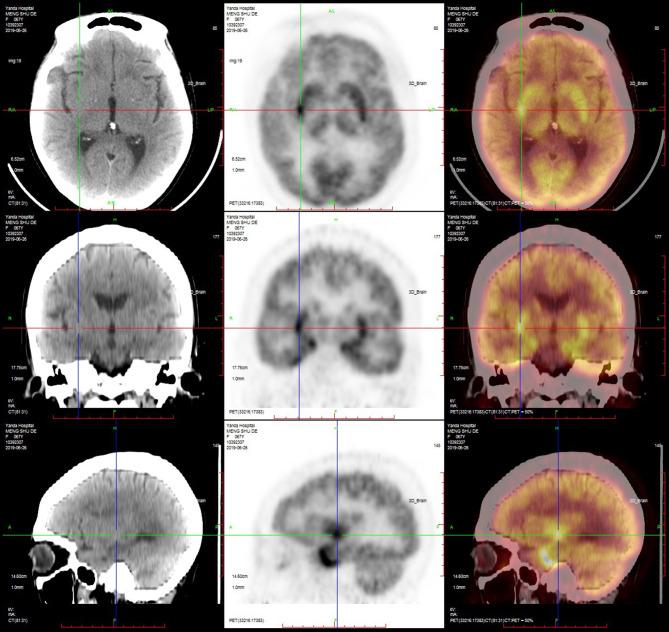

Anti-GABA-B (gamma aminobutyric acid-B) receptor encephalitis is an autoimmune disease mediated by GABA-B-related antibodies. To fully understand the disease, we collected clinical data from patients with GABA-B receptor encephalitis and conducted an analysis to draw conclusions. All patients with GABA-B receptor encephalitis from the Neurology Department of Beijing Tiantan Hospital, affiliated with Capital Medical University, from August 2015 to September 2019 were accepted as study subjects. The clinical data of the patients were analyzed retrospectively and included the general demographic characteristics, clinical manifestations, and auxiliary examinations, including laboratory results, electroencephalograms (EEGs), brain magnetic resonance imaging (MRI), and positron emission tomography (PET-CT) results, as well as treatments. From August 2015 to September 2019, 14 cases of anti-GABA-B receptor encephalitis were diagnosed. Among these patients, middle-aged and elderly men were the main demographic, with an average age of 52 years; moreover, the onset of the disease was relatively sudden, and the time from onset to diagnosis was ~1 month. The main clinical symptoms were frequent epileptic seizures, cognitive dysfunction, and mental behavioral disorders. In seven (50%) patients, the leukocyte in cerebrospinal fluid (CSF) were increased. Five (36%) patients had elevated cerebrospinal fluid protein. In most patients, the oligoclonal bands (83%) of CSF were positive, and 24 h IgG levels (92%) were increased. Anti-Hu or anti-Yo antibodies were positive in two (14%) patients. Tumor markers in 10 (71%) patients indicated that neuron-specific enolase, gastrin-releasing precursor, non-small cell lung cancer-related antigen, or carcinoembryonic antigen levels were increased. EEG results often indicated slow waves, sharp waves, or spike waves in temporal areas. Brain MRI always showed high T2 signals in the medial temporal lobe, hippocampus, and amygdala and swelling in the medial temporal lobe and hippocampus. PET-CT scans almost showed abnormal metabolism in the hippocampus and temporal lobe. Three (21%) patients who underwent systemic PET-CT showed hypermetabolism in pulmonary parenchymal nodules and enlargement of mediastinal lymph nodes. All patients underwent high-dose hormone therapy or immunoglobulin immunotherapy. After treatment, the symptoms of epilepsy, cognitive disorders, and mental behavioral disorders improved to varying degrees. However, one patient died of lung cancer. Anti-GABA-B receptor encephalitis mainly occurred in middle-aged and elderly men, and the disease onset was relatively sudden. Before disease onset, some patients experienced fever and non-specific respiratory symptoms, which mainly manifested as frequent epileptic seizures, cognitive dysfunction, and abnormal mental behavior. MRI and PET-CT revealed abnormal signals and local metabolism, respectively, in the temporal lobe. Moreover, the disease has a close relationship with lung cancer, which requires long-term follow-up observation.

抗GABA - B(γ-氨基丁酸B)受体脑炎是一种由GABA - B相关抗体介导的自身免疫性疾病。为全面了解该疾病,我们收集了GABA - B受体脑炎患者的临床资料并进行分析以得出结论。2015年8月至2019年9月首都医科大学附属北京天坛医院神经内科的所有GABA - B受体脑炎患者均被纳入研究对象。对患者的临床资料进行回顾性分析,包括一般人口统计学特征、临床表现及辅助检查,后者包括实验室检查结果、脑电图(EEG)、脑磁共振成像(MRI)、正电子发射断层扫描(PET - CT)结果以及治疗情况。2015年8月至2019年9月,共诊断出14例抗GABA - B受体脑炎患者。这些患者中,中老年男性为主,平均年龄52岁;疾病起病相对突然,从起病到诊断的时间约为1个月。主要临床症状为频繁癫痫发作、认知功能障碍及精神行为障碍。7例(50%)患者脑脊液(CSF)白细胞增多。5例(36%)患者脑脊液蛋白升高。大多数患者CSF的寡克隆带(83%)呈阳性,24小时IgG水平(92%)升高。2例(14%)患者抗Hu或抗Yo抗体呈阳性。10例(71%)患者的肿瘤标志物显示神经元特异性烯醇化酶、胃泌素释放前体、非小细胞肺癌相关抗原或癌胚抗原水平升高。EEG结果常显示颞叶有慢波、尖波或棘波。脑MRI总是显示内侧颞叶、海马和杏仁核T2信号增高以及内侧颞叶和海马肿胀。PET - CT扫描几乎均显示海马和颞叶代谢异常。3例(21%)接受全身PET - CT检查的患者显示肺实质结节代谢增高及纵隔淋巴结肿大。所有患者均接受了大剂量激素治疗或免疫球蛋白免疫治疗。治疗后,癫痫、认知障碍及精神行为障碍症状均有不同程度改善。然而,1例患者死于肺癌。抗GABA - B受体脑炎主要发生于中老年男性,起病相对突然。发病前部分患者有发热及非特异性呼吸道症状,主要表现为频繁癫痫发作、认知功能障碍及精神行为异常。MRI和PET - CT分别显示颞叶有异常信号及局部代谢异常。此外,该疾病与肺癌关系密切,需要长期随访观察。